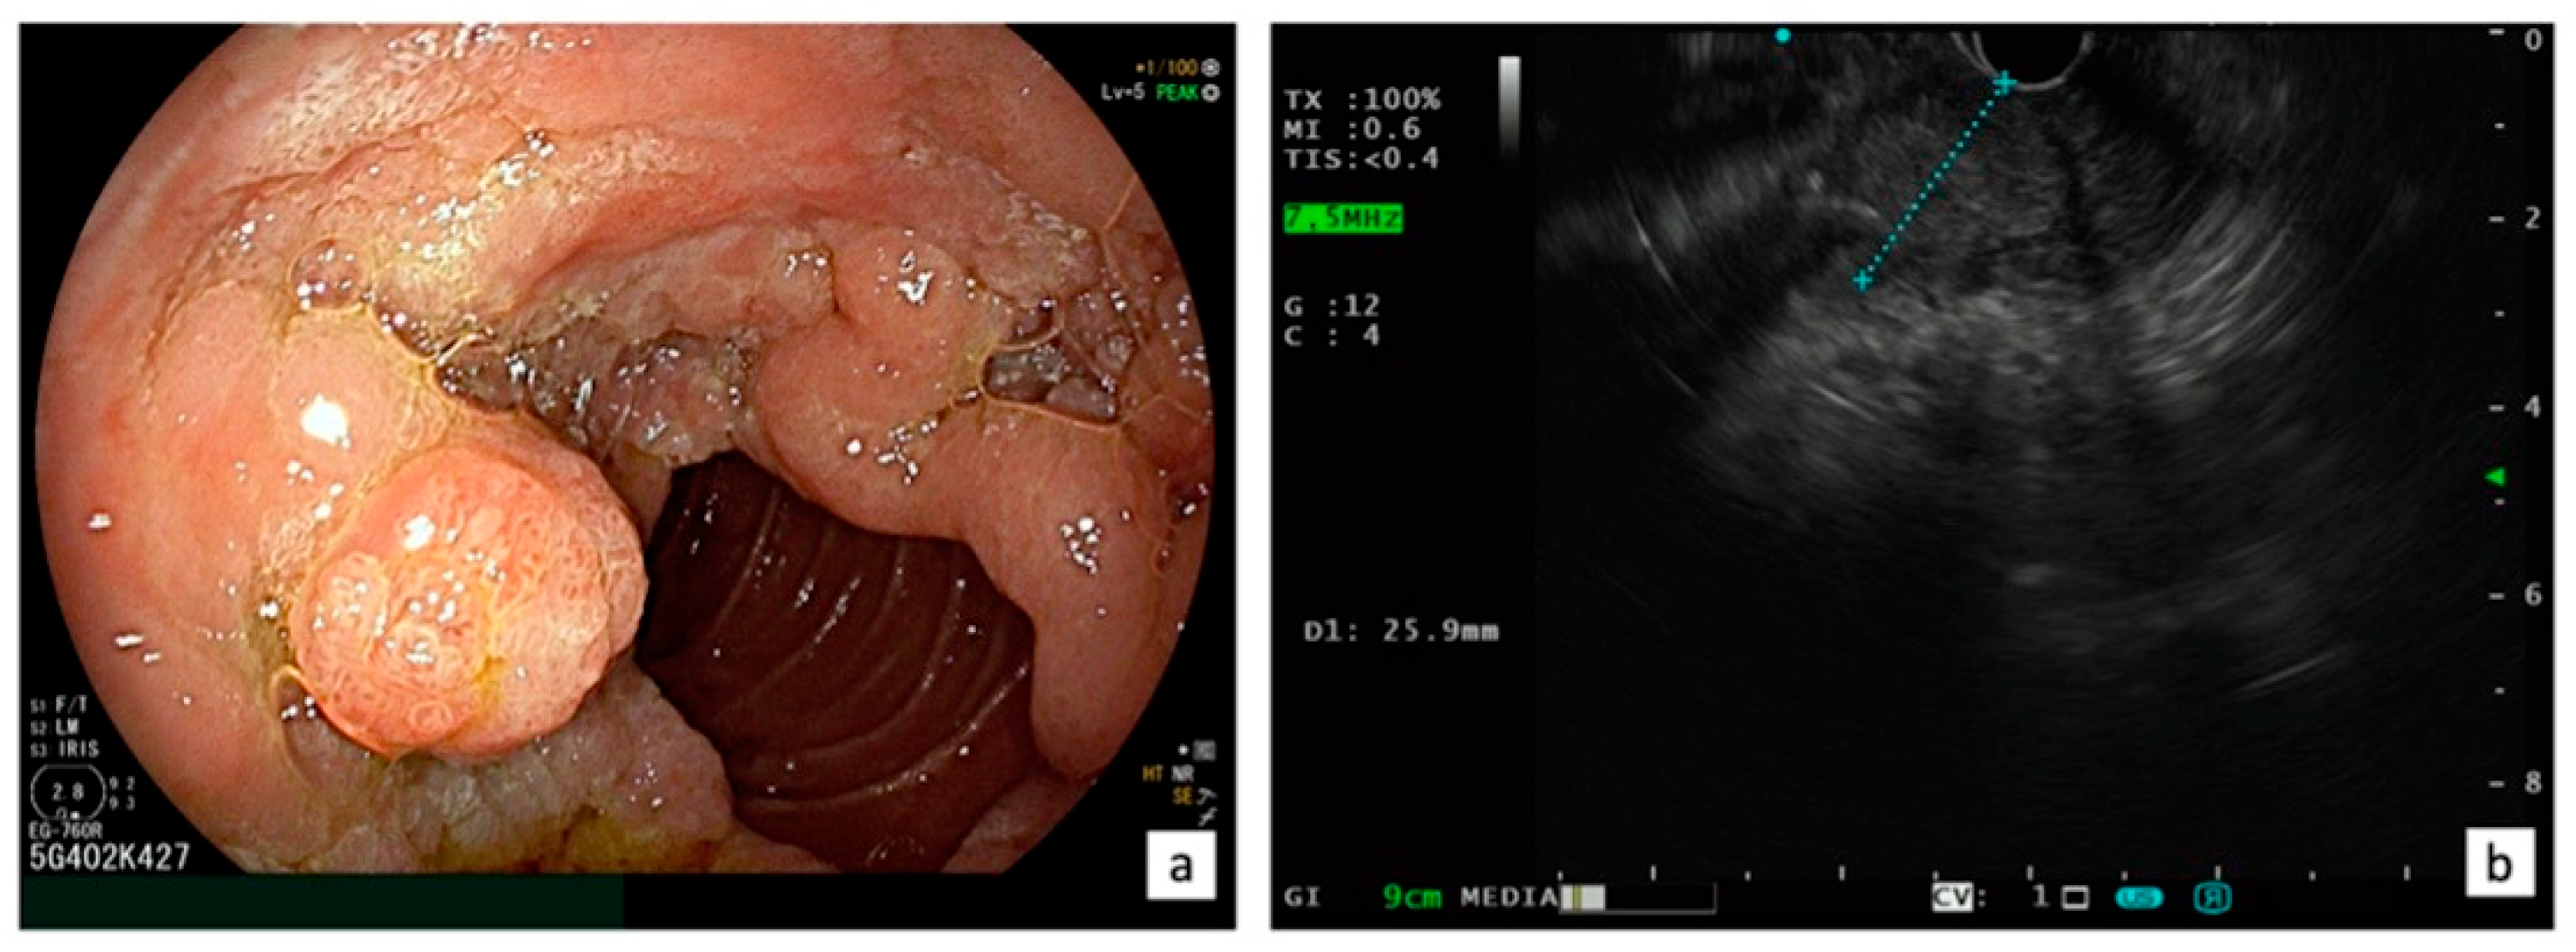

Presently, there is a lack of RCTs that compare EP and surgical treatments, such as transduodenal ampullectomy or pancreaticoduodenectomy, for ANLs. In a recent systematic review and meta-analysis, including a total of 39 studies with 1753 patients (1468 EP and 285 transduodenal ampullectomy), Garg et al. [75] aimed to compare long-term recurrence of benign sporadic ANLs after EP and transduodenal ampullectomy, showing that endoscopic and surgical ampullectomy have similar recurrence rates at 1, 2, 3, and 5 years of follow-up. Thus, when feasible, EP is considered the first choice for ANL. However, there are still situations where surgery remains a viable option for ANL, including the following: (1) intraductal involvement (>20 mm); (2) technical limitations (the presence of a diverticulum or the tumor size exceeding 4 cm); (3) incomplete resection after EP (positive margins); and (4) local recurrence not endoscopically treatable [76] (Figure 3). A systematic review, which included five retrospective cohort studies with 466 patients, revealed that surgical resection (transduodenal ampullectomy or pancreaticoduodenectomy) had better outcomes in achieving complete resection of ANLs compared to EP (risk difference [RD] −0.37, 95% CI −0.50 to −0.24, p < 0.001, I 2 = 71%) without any difference in complications [77]. However, when utilizing a fixed effects model, EP exhibited a lower rate of adverse events (RD −0.28, 95% CI −0.39 to −0.18, p < 0.001; I 2 = 95%) [77].

Indication for surgical treatment: LST-p characterized with a circumferential extra-papillary component on the duodenal wall with a tumor size exceeding 4 cm (a) and an intraductal involvement >20 mm confirmed using EUS (b).